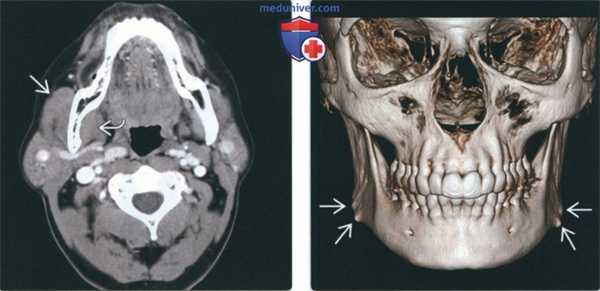

(Слева) При КТ с КУ в аксиальной проекции наблюдается асимметричное увеличение правой жевательной и медиальной крыловидной мышц, случайная находка. Плотность и интенсивность накопления контраста не отличаются от мышц противоположной стороны.

(Слева) На аксиальной КТ с КУ определяется асимметричное увеличение жевательной мышцы и медиальной крыловидной мышцы права. Характер контрастирования и плотность этих мышц аналогичны мышцам на противоположной стороне.

(Справа) На 3D КЛКТ у пациента с бруксизмом в анамнезе определяется выбухание и деформация углов нижней челюсти с обеих сторон. Неровный контур имитирует картину экзостозов в области прикрепления жевательных мышц и ремоделирование копи вследствие гиперактивности мышц.

(Справа) Фото пациента с доброкачественной односторонней гипертрофией жевательной мышцы. Обратите внимание на значительное выбухание правой щеки, обусловленное гипертрофией жевательной мышцы.